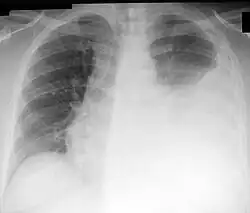

Рентгенологически линии Дамуазо соответствует граница затемнения, обусловленного жидкостью в плевральной полости[5].